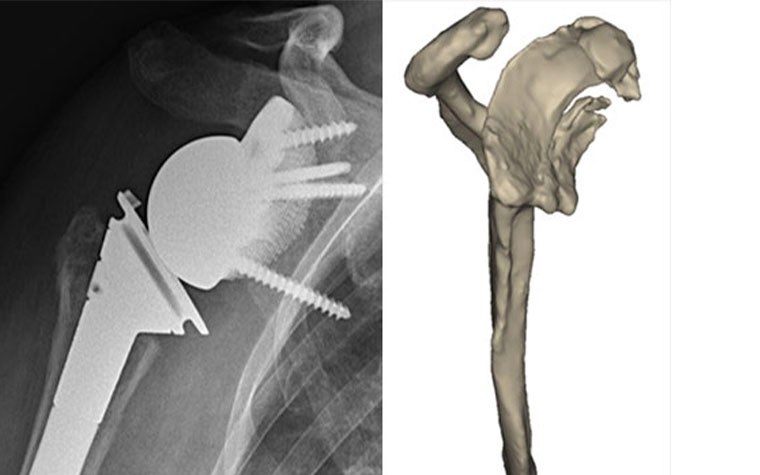

After analysis of the medical images indicating devastating shoulder arthrosis with severe medialization and complete loss of the glenoid vault, Dr. Van den Bogaert decided that implantation of a classic pegged baseplate for reverse total shoulder was not an option in this case.

Dr. Van den Bogaert worked with Materialise’s clinical engineering team to define the best design for the custom-made glenoid implant, which included a baseplate for a reverse shoulder replacement prosthesis augmented with a porous structure exactly matching the patient’s glenoid cavity.

Preoperative planning included optimizing the baseplate's position to reconstruct the joint center of rotation to an anatomical position as much as possible. In addition, screw position and orientation were fully customized, to address the strongest parts of the (remaining) scapular bone.

The custom-made titanium implant was manufactured with 3D printing. Next, 3D-printed, personalized guides were designed to guide the accurate positioning of the implant, the pre-drilling of the screw holes, and the fixating of the screws during surgery. The custom-made instruments greatly facilitate the intervention by allowing surgeons to accurately transfer the preoperatively planned component placement and screw positioning during surgery.